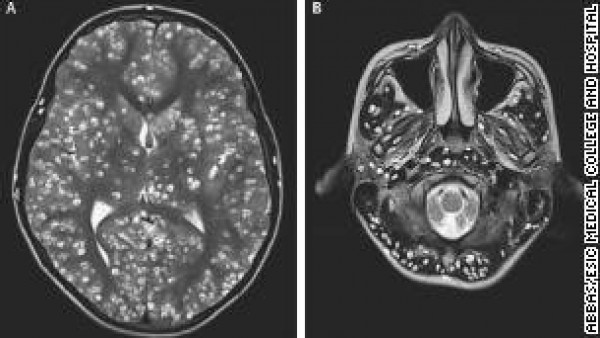

وذهب الرجل إلى أحد الأطباء، الذي طلب القيام ببعض الفحوصات الطبية، فعثر على دودة شريطية في مخ الرجل ناتجة عن تناوله اللحم نيئا وعدم تعريضه إلى المزيد من الحرارة.

وأكد الطبيب أن تلك الدودة هي السبب في إصابة الرجل بتشنجات لأنها عملت على الإصابة بخلل في وظائف المخ، ونصحه بطهي الطعام وتسخينه أكثر وعدم تكرار ما فعله مرة أخرى.